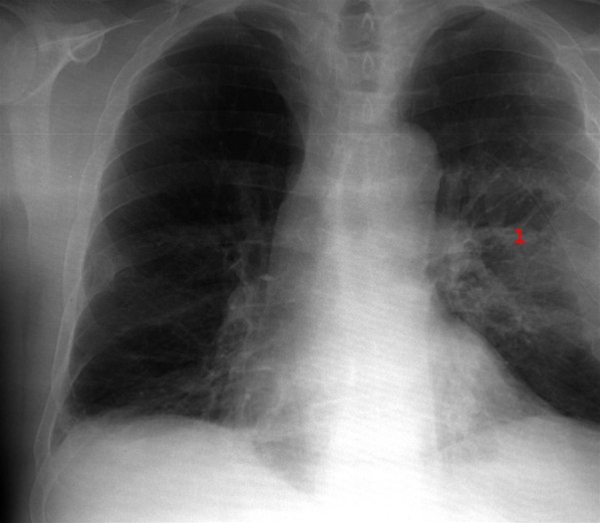

Restforandringer efter behandling af venstresidig lungeabsces (1).